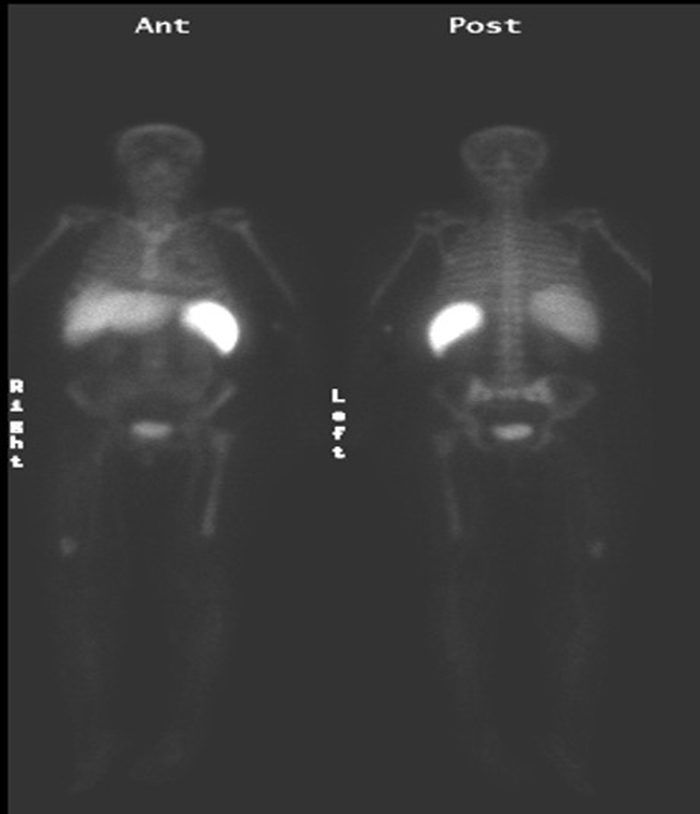

Focal intense activity seen in the right antecubital region and along the right lateral abdominal wall on Tc-99m MDP scan is related to extravasation of radiopharmaceutical at the injection site with scatter of photons from the forearm to the abdominal wall (narrow angle scatter). |